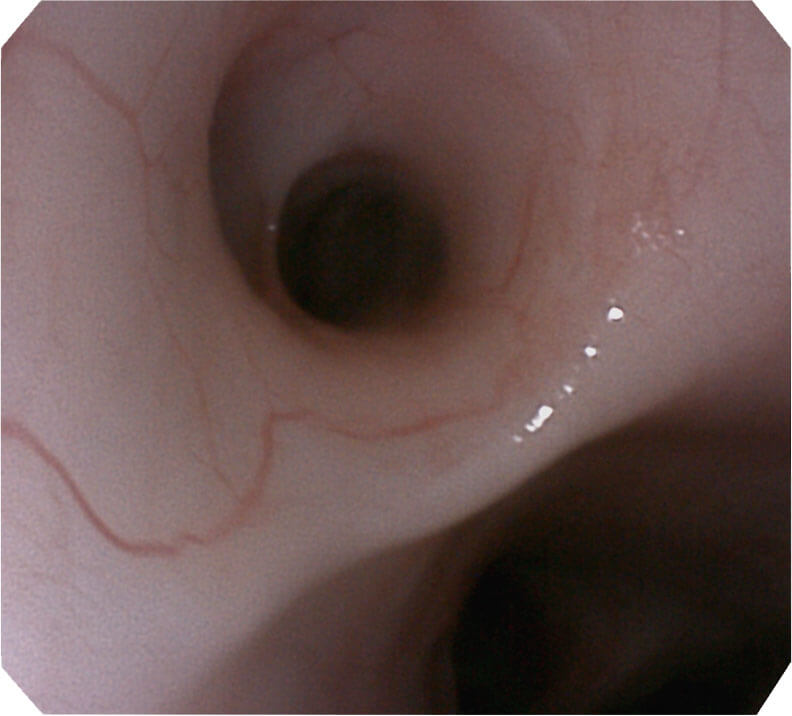

帮助医生更加清晰地观察气管表面病灶

光电复合染色成像技术(VIST)是一种光学滤波和数字滤波相结合的染色成像技术,摒弃了滤光转轮而直接采用光谱组合的方案,加入了血红蛋白吸收高峰与次高峰的蓝紫光和绿光光谱,更有利于黏膜血管吸收,突显浅表层血管和中层血管的对比度,因而具备更高的图像对比度,有助于观察微细结构变化及病灶边界的观察。